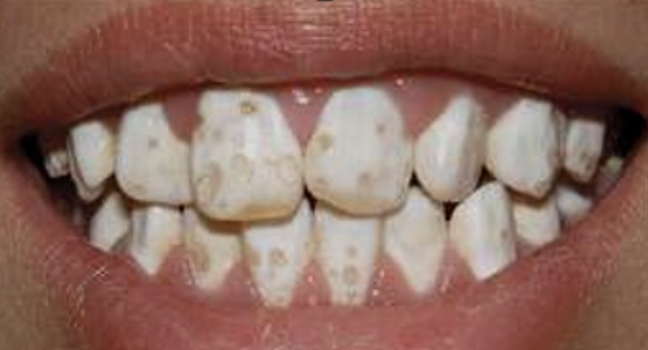

Welke typen amelogenesis imperfecta zijn er?

Hypoplasie en hypocalcificatie.

Wat is hypoplasie?

Hierbij is er een onvolledig ontwikkeld glazuur. Er was dus een stoornis in de vorming.

Wat is hypocalcificatie?

De vorming zelf is normaal maar er is een stoornis in de calcificatie. Er is iets fout gegaan bij de ameloblasten, die dit opbouwen. De vormins is goed maar er mist iets in de mineralisatie.